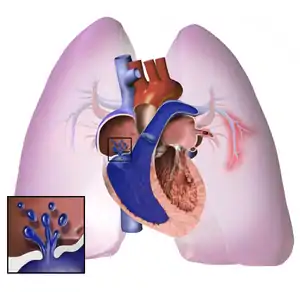

The pathogenesis of pulmonary arterial hypertension (WHO Group I) involves the narrowing of blood vessels connected to and within the lungs. This makes it harder for the heart to pump blood through the lungs, as it is much harder to make water flow through a narrow pipe as opposed to a wide one. Over time, the affected blood vessels become stiffer and thicker, in a process known as fibrosis. The mechanisms involved in this narrowing process include vasoconstriction, thrombosis, and vascular remodeling (excessive cellular proliferation, fibrosis, and reduced apoptosis/programmed cell death in the vessel walls, caused by inflammation, disordered metabolism and dysregulation of certain growth factors).[25][26] This further increases the blood pressure within the lungs and impairs their blood flow. In common with other types of pulmonary hypertension, these changes result in an increased workload for the right side of the heart.[12][27] The right ventricle is normally part of a low pressure system, with systolic ventricular pressures that are lower than those that the left ventricle normally encounters. As such, the right ventricle cannot cope as well with higher pressures, and although right ventricular adaptations (hypertrophy and increased contractility of the heart muscle) initially help to preserve stroke volume, ultimately these compensatory mechanisms are insufficient; the right ventricular muscle cannot get enough oxygen to meet its needs and right heart failure follows.[12][26][27] As the blood flowing through the lungs decreases, the left side of the heart receives less blood. This blood may also carry less oxygen than normal. Therefore, it becomes harder and harder for the left side of the heart to pump to supply sufficient oxygen to the rest of the body, especially during physical activity.[28][29][20]

Pathogenesis in pulmonary hypertension due to left heart disease (WHO Group II) is completely different in that constriction or damage to the pulmonary blood vessels is not the issue. Instead, the left heart fails to pump blood efficiently, leading to pooling of blood in the lungs and back pressure within the pulmonary system. This causes pulmonary edema and pleural effusions.[31] In the absence of pulmonary blood vessel narrowing, the increased back pressure is described as 'isolated post-capillary pulmonary hypertension' (older terms include 'passive' or 'proportionate' pulmonary hypertension or 'pulmonary venous hypertension'). However, in some patients, the raised pressure in the pulmonary vessels triggers a superimposed component of vessel narrowing, which further increases the workload of the right side of the heart. This is referred to as 'post-capillary pulmonary hypertension with a pre-capillary component' or 'combined post-capillary and pre-capillary pulmonary hypertension' (older terms include 'reactive' or 'out-of-proportion' pulmonary hypertension).[11][14][32]